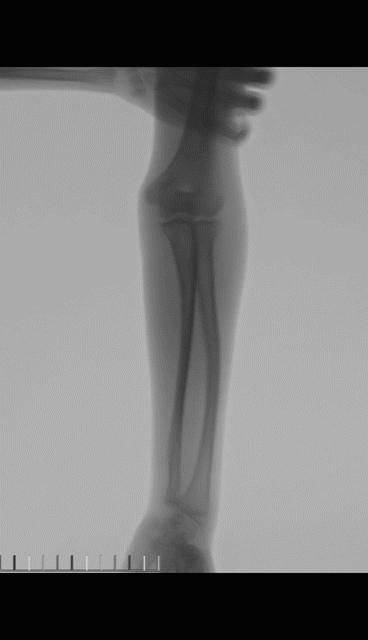

老师: 下面两个病例,分别是9岁4个月男孩的前臂中段骨折,保守治疗后3个月骨折对位、愈合良好。另外一个12岁男孩,早期外院保守治疗,三周时骨折再移位,于我院再次整复后恢复满意。